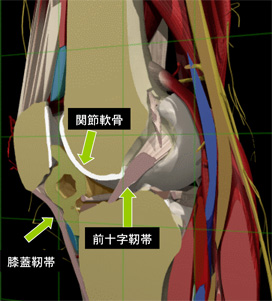

膝の組織について

膝の組織をご説明します。

この絵を参考にしていただければ、下記の障害について、どの部分が障害を受けているのかわかりやすいと思います。

ジャンパー膝

シェーマにも示した膝蓋靭帯の膝蓋骨付着部への繰り返される牽引力が原因です。